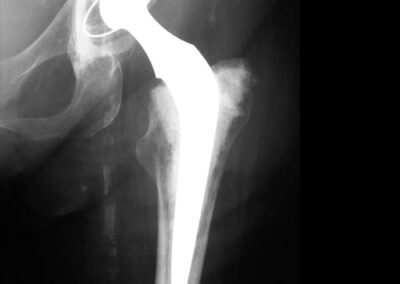

Exemplos de artroplastia cimentada e não-cimentada podem ser vistos na Fig. 2, através das radiografias. A figura ainda mostra exemplos radiográficos de artroplastias híbrida (haste femoral cimentada e componente acetabular não-cimentado) e híbrida-reversa (haste femoral não-cimentada e componente acetabular cimentado). O sucesso da artroplastia total de quadril depende basicamente de três fatores críticos: escolha do paciente, do implante e da técnica cirúrgica. Provavelmente, o determinante isolado mais importante seja a escolha apropriada do paciente. A escolha de um paciente inadequado pode comprometer o design mais avançado ou mesmo o cirurgião mais experiente (1,2,7).